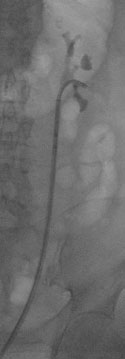

![]() |

| Starres Endoskop in der Niere | Starres Endoskop in der Niere |